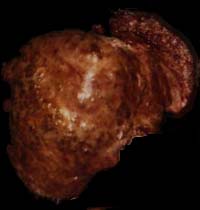

My need for a liver transplant became a reality in AUG 94 after finding that I had asymptomatic Hep-C combined with chronic alcoholic liver disease and had burst varices in my liver. I was sick and bled out and nearly dead but rebounded enough in two months to enter a recovery center and get on with trying to save my hide from the Hep Dragon and the Grim Reaper. At six months sober, I was evaluated by the UWMC transplant team. Evaluation and testing took 2 months and then I was placed on the type B liver transplant list as number two. Then the waiting began as I watched myself wasting away and getting sicker and more forgetful every day for the next 11 months. I was called at home and told to get right down to the hospital on 16FEB96 0900hrs. I was flustered and scared to death and didn't really want to go. When I got to the UWMC, University of Washington Medical Center, I was immediately so busy with preperation that I honestly did not have another chance to think about being scared. Drugs, showers, enemas, shaving, answering myrid questions, trying to memorize everyone's name. No pain, though. No painful procedures were done until I was knocked out at about 1500hrs. I woke up in the ICU the next morning. My wife and my mother were there waiting for me to regain consiousness. Yes, there was some pain but not anything unbearable. The only thing I found unbearable was the resperator and my incredable thirst. I tried to take the resperator out but my mother and the nurse stopped me. Later, I wrote a message to my mom and told her to go home and get some rest. While everyone had their back turned I pulled that damnable thing out. Then I demanded some ice chips or threatened to go get my own and I was in deadly earnest. What a relief those cool, wet chips gave me! I noticed the first sign of recovery the minute I awakened in ICU. The bursitis pain in my shoulders was completely gone! I don't know if it is the prednesone or my new liver functioning but it was a great relief! Also, I was completely helpless and dependant on everyone for the slightest thing. With no stomach muscles, I couldn't even shift in bed by myself. My kidneys shut down for a while and the inevitable swelling was difficult for a few days. I guess swelling of the privates is very common for men and women and damned uncomfortable, too. Sleeping on my back was never an option for me. I just can't do it! The minute I close my eyes, my soft palette falls back and I begin to choke. On top of that, the drugs were making me see the most terrible visions you could imagine. The second I closed my eyes all I could see was white tile floors, blood, slaughter, inhumanity, torture, sadism of every possible description done to all kinds of people. I truely thought I was going insane. These horrific images couldn't possibly come from a sane mind! I was given powerful drugs to try to relieve these images but nothing helped. I spent the first two weeks without sleep on my aching back. I was talking to people who weren't there, begging for some relief and some rest. Without the support of my wife and my mother I think I would have given up hope of recovery. My emotional state was pathetic. I was laughing and crying at the same time and had no control over anything. I couldn't watch TV or talk about anything upsetting. The first morning, I looked out the window with hazy eyes at a leafless tree dripping with cold Seattle rain. I immediately thought of a funeral under those gray, lifeless clouds with people mourning and grieveing and I just plain lost it for about two hours. I was sobbing non-stop and no consolation could make me feel any better. Fear becomes a tangible thing. There is just no way to explain this and I don't know if I will ever come to grips with it. It isn't fear of rejection or of change or of pain but instead a raw physical thing that makes my hair stand on end. I'm presently seeking professional psychiactric aid in dealing with this. Being the eternal optimist, I also expect to overcome my fear with time. After saying all this, I am assured that I am very fortunate. I was released from the hospital after only 12 days and am now taking care of myself quite well. Physically, I am stronger and better every day. I really do not know if I would face this operation twice but pain and suffering quickly fade from experience. I'm glad I had the transplant and I'm not about to waste valuable time worring about the what if's of rejection and the possibility of acute Hep-C attack. I just keep a weather eye on my labs and that's good enough. Yes, neurologigal damage is a possibility but that can mostly be reversed with therapy or ignored with practice. I don't know if my taste buds or the feeling in my left arm will ever come back but neither one is essential to my living life to the fullest even on a tight meds schedule. The five P's (Proper Planning Prevents Poor Performance) might be here forever as I now have to plan like Napolean to go anywhere or do anything but it doesn't have to be an end to life as I know it. Cards, letters and E-mail piled up daily while I was in the hospital and Alice and I had some good cathartic cries while reading them. Small things make me happy every day. Getting up in the morning, taking a shower by myself, going through the rituals of daily life. Next week I can drive again and the week after I'll be going back to work. I am easily tired out but daily mild exercise helps. So does seeing and talking to friends and relatives and knowing how much everyone has been concerened with my progress. I required constant care at home for two weeks while I recovered. My wife took a week off from work and my mother came to stay with us for another week after that. I would almost certainly be back in the hospital without their help in maintaining my schedule, going to the drug store for my first $3000 in drugs, making my meals, holding my hand and doing gererally distasteful step-n-fetchit tasks for me. Now I believe in Angels. Prednesone heebie-jeebies are nothing to sneeze at. Forwarned is forarmed, though. Nothing that can't be gotten through with. I practiced relaxation techniques and some of them actually worked along with certain medications. I'm still not fit to talk to until after noon. My advice for anyone awaiting a transplant? Do it! Nothing is so rewarding as a second chance at life. Hope is always better than dispair. ;-) Make your world a better place, and join me in that hopeful future if you have that chance. Your friends and loved ones will thank you. Feel free to add any other cliches as you see fit.YMMMV. Very best regards and a big {{{{{{{HUG}}}}}}}}. ODAAT Shinin' thru in Seattle, Uncle Dave